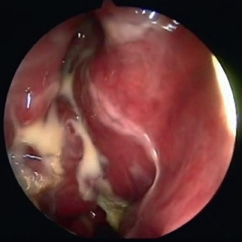

Bei erkennbaren entzündlichen Komplikationen kann durch eine zeitnahe rhinochirurgische Behandlung mit Entlastung des entzündeten Sinus eine Lockerung und ein möglicher Implantatverlust vermieden werden (Abb. 14a und b). Eine interdisziplinäre Abstimmung wird hier dringend angeraten [18–20].

Prof. Dr. O. Kaschke